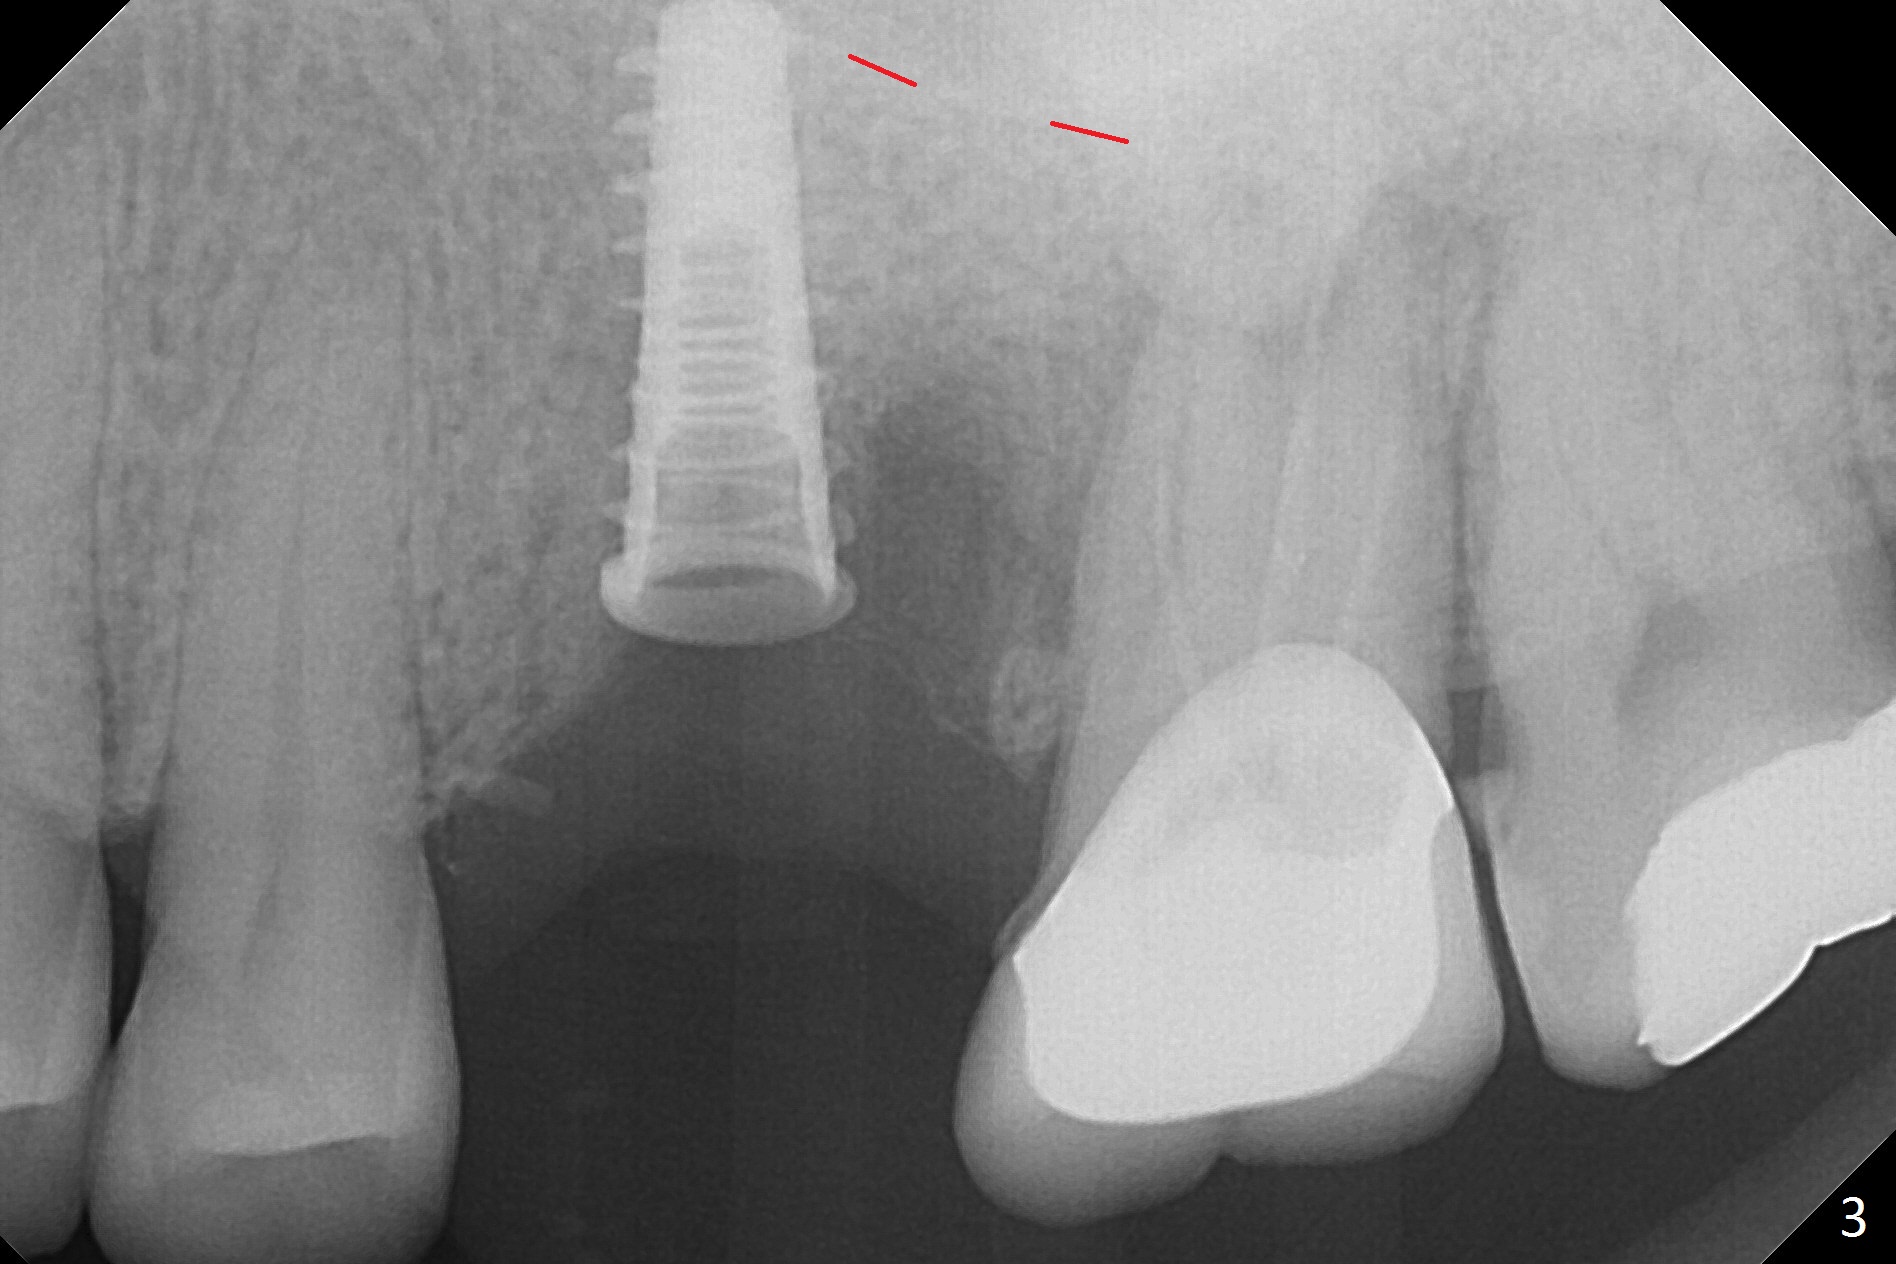

Magic Split is used to start access (flapless) and initial bone expansion at #14. The split does not go deep, since bone density is high in the deep portion. A 1.6 mm drill has to be used for 13 mm (Fig.1). Note the low bone density in the distobuccal socket (*). Later the osteotomy extends to 15 mm (gingival level). After 3.8 mm Magic Drill (MD) for 15 mm, a 4x11 mm dummy implant is placed with insertion torque of 60 Ncm (implant motor, Fig.2). After 4.3 mm MD, a 4.5x11 mm IBS implant is placed with insertion torque of 60 Ncm for implant motor >40 Ncm for torque wrench (Fig.3). The implant seems to be placed deep, but the buccal plate feels to be low. Following bone graft buccally, especially distobuccal (Fig.4,5 ^), a 5x4(3) mm abutment is placed. The buccal gingiva is torn during bone graft (Fig.6 >). Periodontal dressing is applied around the abutment (for increased retention) for wound protection.